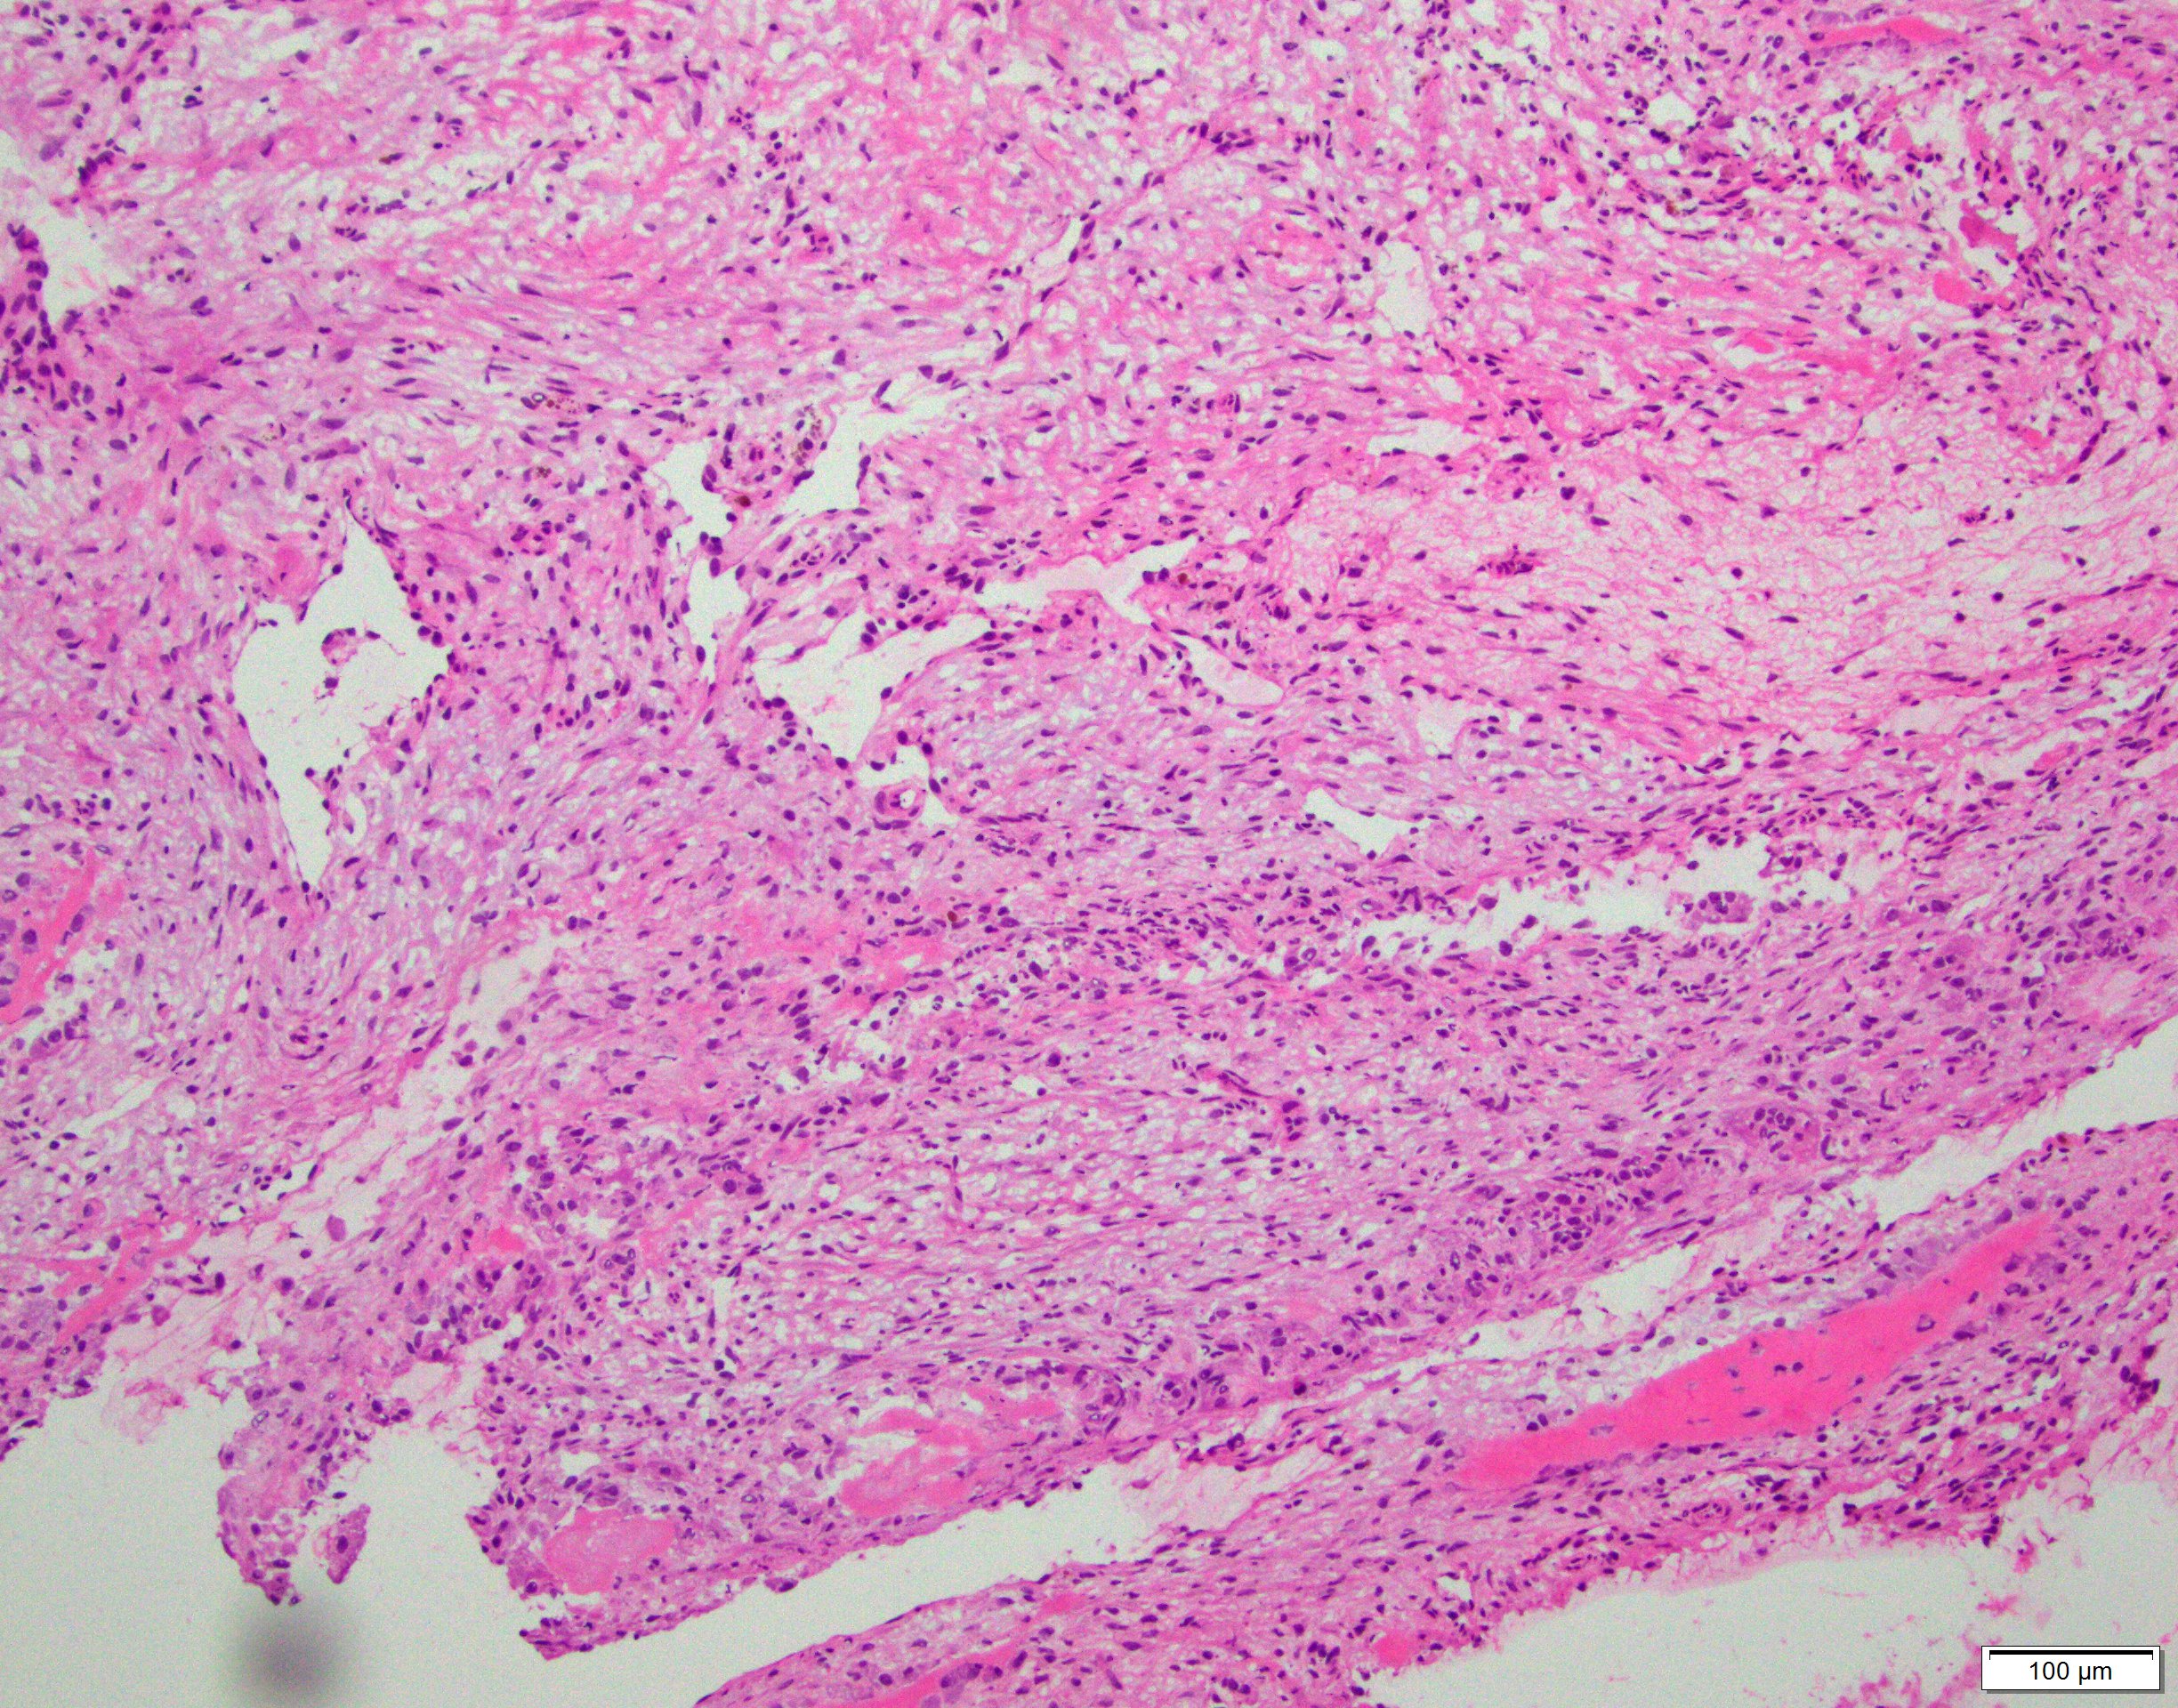

Microscopic (histologic) description

- Multiloculated cystic lesion

- Blood filled cystic spaces separated by cellular septa containing fibroblasts, giant cells and woven bone

- Calcified, basophilic material (blue reticulated chondroid-like material)

- Necrosis not common but mitotic activity is easily identified

- No cytologic atypia (Am J Clin Pathol 2015;143:823)

- Numerous giant cells in connective tissue that line large sinusoidal spaces

Microscopic (histologic) images

Contributed by Elham Nasri, M.D. and Kelly Magliocca, D.D.S., M.P.H.